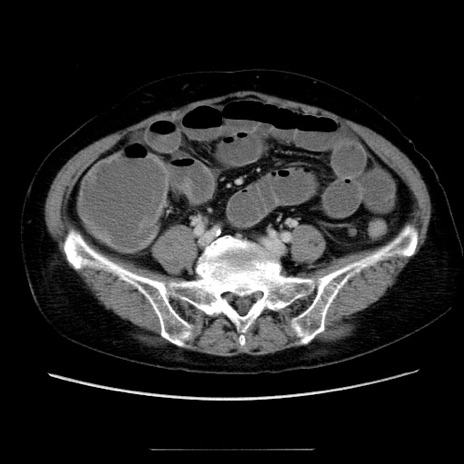

冠状断像

【症例】70歳代女性

【主訴】お腹が張る

【現病歴】1週間くらい前から腹部膨満の自覚あり。昨日夜から増悪したため、本日救急外来受診。

【身体所見】意識清明、BT 36.5℃、BP 165/106mmHg、HR 80bpm、SpO2 98%、腹部:膨満、軟、自発痛・圧痛なし、触診にて不快感あり、腸蠕動音:減弱

【データ】WBC 12600、CRP 1.04